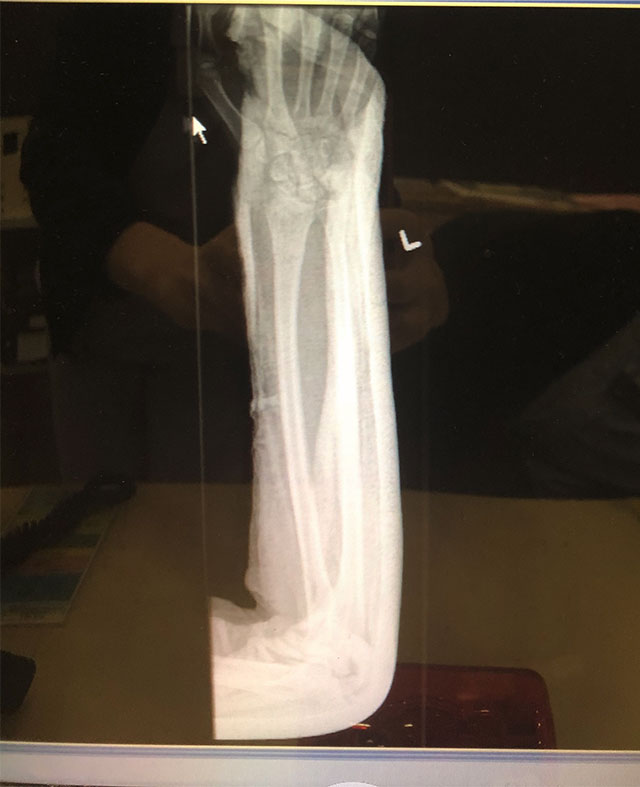

骨折一定要打鋼板嗎?

15歲男子將近發育完成。若果骨科專科醫生建議骨折傷勢嚴重需要接受手術治療,一般效果都理想。若果想在骨折癒合後取出鋼片,一般會在手術後九個月至一年時間進行。祝早日康復。